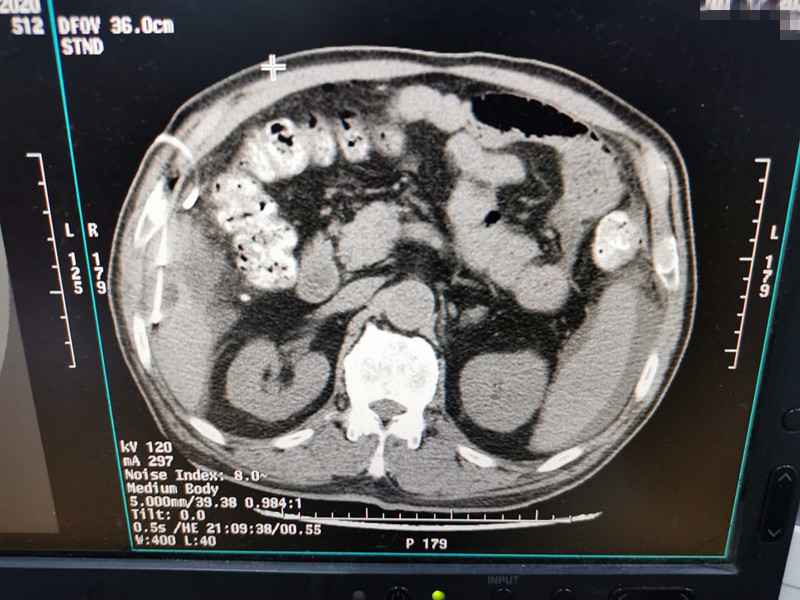

83岁肺部氩氦刀冷冻消融

发布人:美国氩氦刀技术官方网站    发布时间:2020/7/20 15:28:22